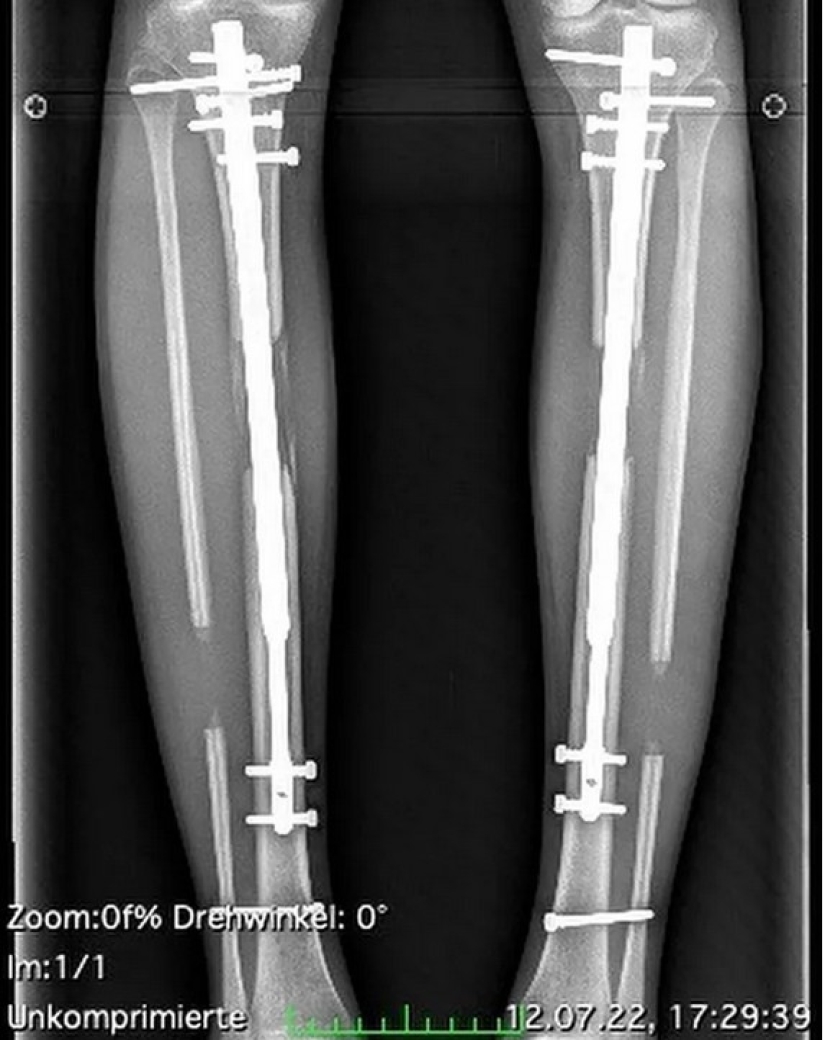

La cirugía de alargamiento de piernas es una operación dolorosa que inquieta a una persona durante mucho tiempo. Esto se debe a que se rompen los huesos de la parte inferior de la pierna, después de lo cual se insertan estructuras metálicas en ellos. Y también es muy caro. La modelo pagó 160.000 dólares (12,7 millones de rublos) por dos cirugías y rehabilitación.